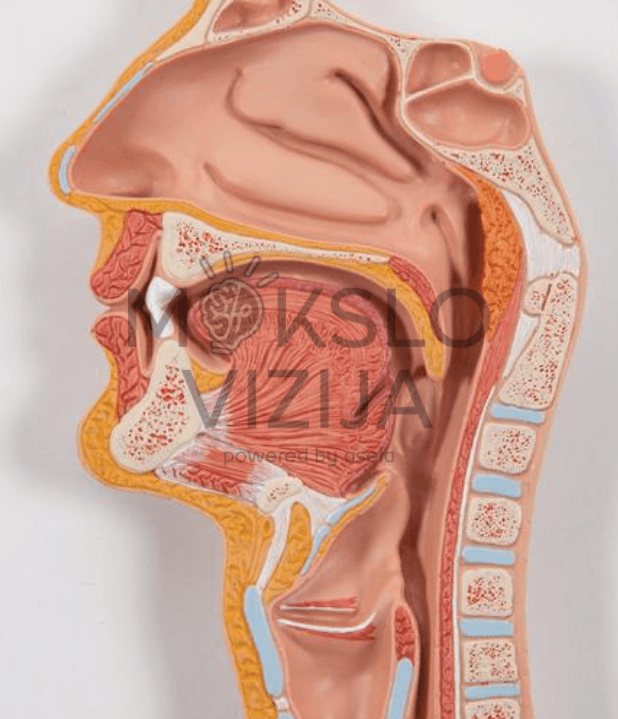

Dešinėje modelio pusėje esantis kepenų ir skrandžio segmentas išimamas, todėl galima apžiūrėti vidaus organų tarpusavio santykį iš kelių kampų. Tokia konstrukcija leidžia lengviau paaiškinti virškinimo proceso eigą ir vidaus organų funkcijas.

Savybės:

- Tiksli žmogaus virškinimo sistemos anatomija nuo burnos iki tiesiosios žarnos

- Nuimamos dalys: kepenys su skrandžio dalimi, atidaromas skrandis

- Matomi vidaus organų paviršiai ir struktūros

Techniniai duomenys:

- Išmatavimai: 81 × 31 × 10 cm

- Svoris: 3,2 kg

- Sudėtis: 3 dalys

- Medžiaga: plastikas